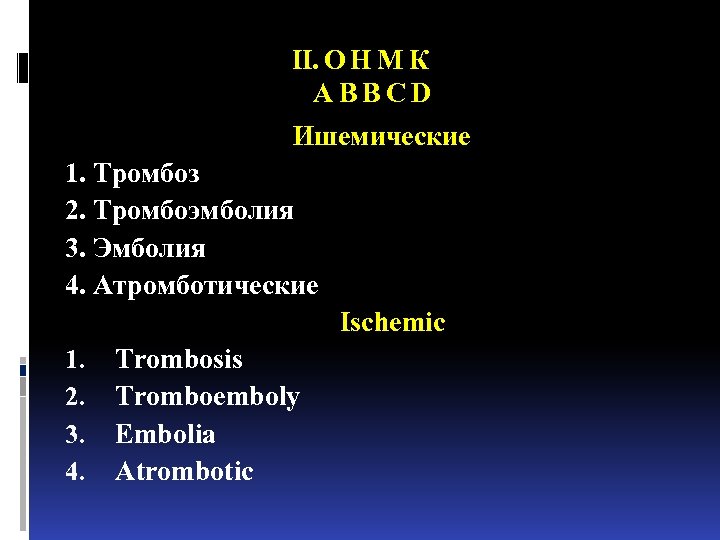

II. О Н М К A B B C D Ишемические 1. Тромбоз 2. Тромбоэмболия 3. Эмболия 4. Атромботические Ischemic 1. Trombosis 2. Tromboemboly 3. Embolia 4. Atrombotic

II. О Н М К A B B C D Ишемические 1. Тромбоз 2. Тромбоэмболия 3. Эмболия 4. Атромботические Ischemic 1. Trombosis 2. Tromboemboly 3. Embolia 4. Atrombotic